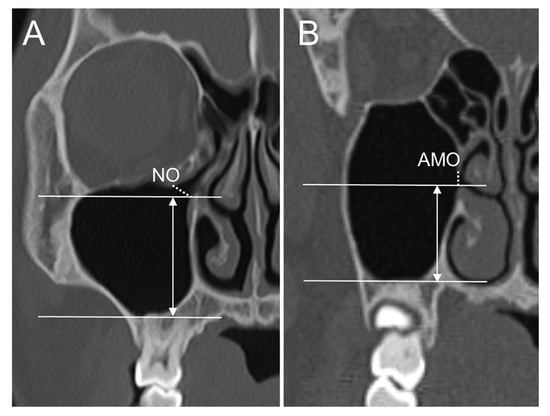

| NO_sup | The most superior point of the NO |

| NO_inf | The most inferior point of the NO |

| NO_ant | The most anterior point of the NO |

| NO_post | The most posterior point of the NO |

| MSF | The most inferior point of the maxillary sinus floor |

| OF | The most inferior point of the orbital floor |

| Location of AMO/NO | |

| AMO_AP location | Distance from the MS_ant to AMO_ant in the antero-posterior direction |

| AMO_SI location_inf | Distance from the MSF to AMO_inf in the supero-inferior direction |

| AMO_SI location_sup | Distance from the OF to AMO_sup in the supero-inferior direction |

| NO_AP location | Distance from the MS_ant to NO_ant in the antero-posterior direction |

| NO_SI location_inf | Distance from the MSF to NO_inf in the supero-inferior direction |

| NO_SI location_sup | Distance from the OF to NO_sup in the supero-inferior direction |